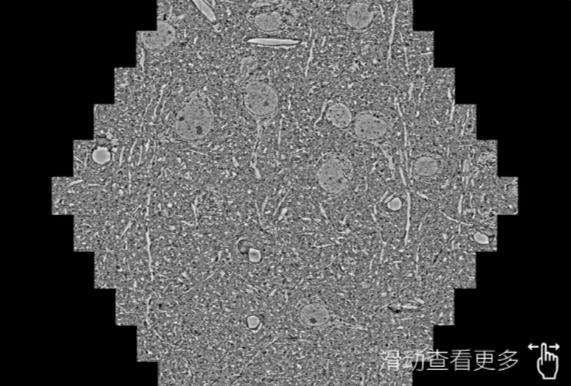

鼠脑切片。左图使用大足蔡司大足扫描电镜MultiSEM706对165μmx143pm面积区域成像,耗时仅需1.5秒。右图为鼠脑切片中30μm区域放大效果。样品由芝加哥大学B.Kasthuri提供。

使用蔡司高速大足扫描电镜MultiSEM对1mm²人脑皮层组织进行高分辨成像,并对其中的各种细胞结构进行三维重构分析。左图展示了2x3mm²组织平面中锥体神经元的三维重构效果。右图显示了局部体积神经元三维重构。图像由哈佛大学chtman实验室提供,渲染图由D. Berger 制作。